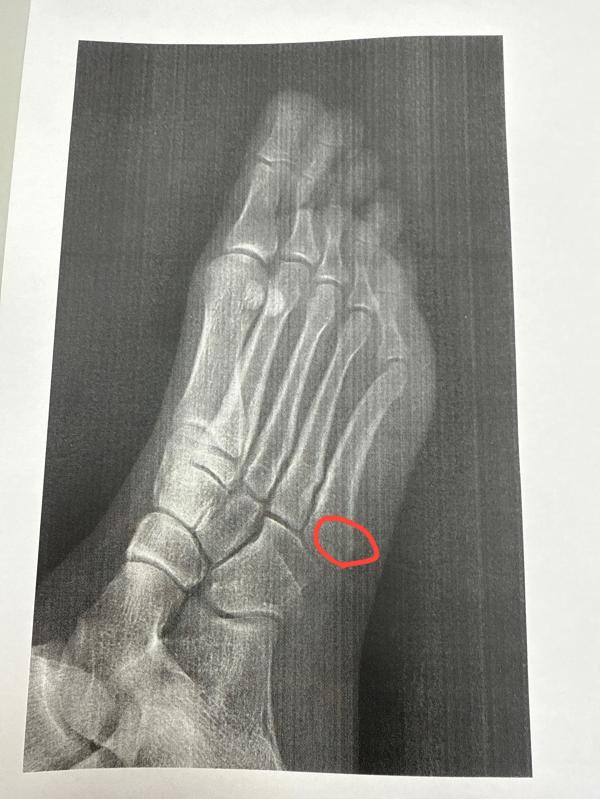

Позавчера в 5:30 встала думаю пойду в туалет, встаю, а ноги ватные/отказывают (либо как отсидела где нибудь их) упала на колено и голеностоп. Перелом..)

Пошла поссать и сломала ногу пипец)🤣